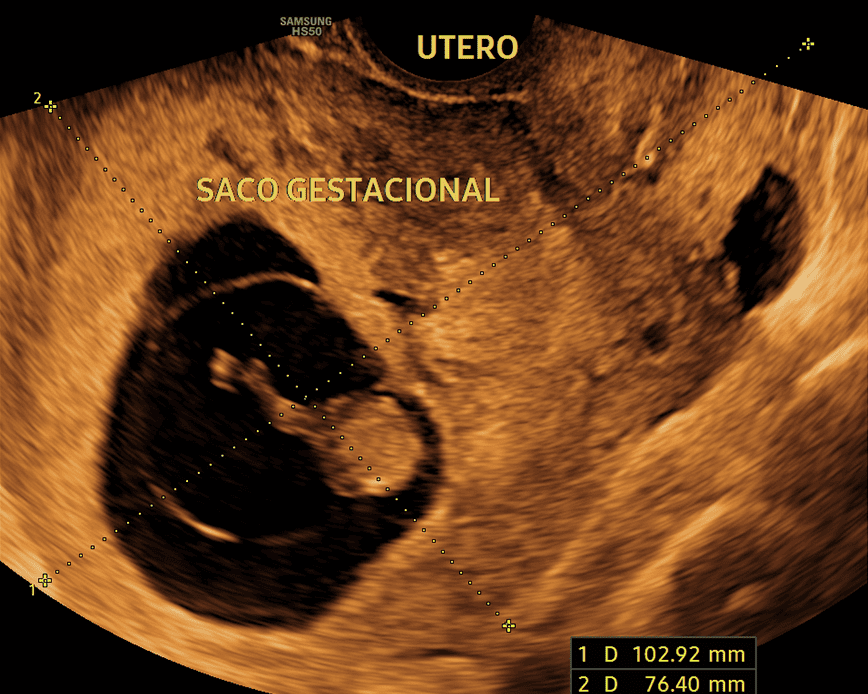

Las ecografías de embarazo son fundamentales para monitorear el desarrollo y bienestar del bebé en cada etapa. Permiten confirmar el embarazo, calcular con precisión la edad gestacional y evaluar el crecimiento fetal. Además, ayudan a detectar posibles anomalías o complicaciones, verifican la posición del bebé y el estado de la placenta, garantizando la salud tanto del bebé como de la madre durante todo el proceso gestacional.

Esta ecografía permite identificar el sexo del bebé con precisión a partir de la semana 12 de gestación. Además, ofrece información sobre el bienestar fetal, la ubicación de la placenta y la cantidad de líquido amniótico, asegurando el monitoreo adecuado del embarazo.

Esta ecografía permite identificar el sexo del bebé con precisión a partir de la semana 16 de gestación. Además, ofrece información sobre el bienestar fetal, la ubicación de la placenta y la cantidad de líquido amniótico, asegurando el monitoreo adecuado del embarazo.